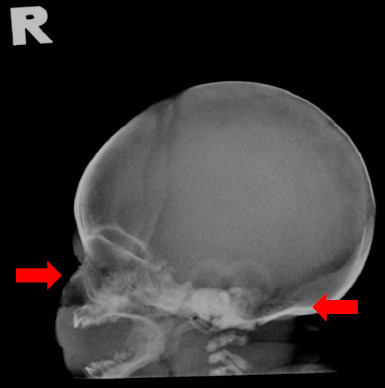

软骨发育不全是一种导致肢体缩短的遗传性疾病,是不成比例侏儒症最常见的形式。产前可通过超声检查诊断,产后可通过临床和放射学检查诊断。目前,越来越多的受影响的胎儿在产前诊断,因为产前超声检查是常规进行在初级保健设置。在此,我们提出一个健康的26岁初产妇,在妊娠晚期,根据她的产前超声检查结果,被诊断为软骨发育不全。出生后,婴儿的临床和放射检查结果证实了这一诊断,显示长骨缩短。本病例强调了在初级保健机构的常规妊娠晚期超声检查中识别软骨发育不全软标记的重要性。软骨发育不全的早期诊断是重要的,以确保及时转诊到三级中心和充分的准备父母为他们的孩子的分娩。

Achondroplasia, a genetic disorder causing limb shortening, is the most common form of disproportionate dwarfism. It can be diagnosed prenatally through sonographic findings and postnatally through clinical and radiological findings. Currently, an increasing number of affected foetuses are diagnosed antenatally since prenatal ultrasonography is routinely conducted in primary care settings. Herein, we present the case of a healthy 26-year-old primigravida who received a diagnosis of achondroplasia for her foetus during the late third trimester based on her prenatal ultrasonographic findings. Following birth, the diagnosis was confirmed by the baby's clinical and radiological findings, which showed shortening of the long bones. This case highlights the importance of recognising the soft markers of achondroplasia during routine third-trimester ultrasonography in primary care settings. Early diagnosis of achondroplasia is important to ensure timely referral to tertiary centres and adequate preparation of parents for the delivery of their baby.